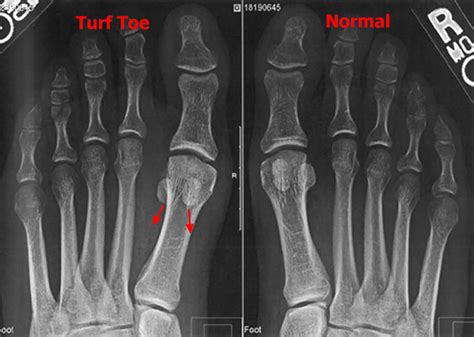

While many mild cases respond well to home care, professional intervention is necessary if the pain does not diminish within 48 to 72 hours, or if the swelling makes it impossible to put on a shoe. A podiatrist or orthopedic surgeon can use imaging studies like X-rays or MRIs to rule out fractures or severe damage to the cartilage that might require immobilization in a boot or, in extreme cases, surgical intervention.